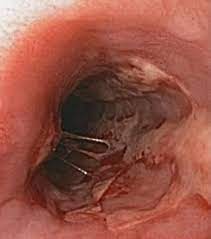

Hsv Esophagitis Vs Cmv Esophagitis - The Radiology Assistant Esophagus I Anatomy Rings Inflammation : „ odynophagia is the predominant presenting symptom.. Unlike herpes esophagitis, cmv esophagitis almost never occurs in immunocompetent patients, and the vast majority of affected individuals are found to have aids. If left untreated, esophagitis can damage the lining of the. In contrast, cmv esophagitis often occurs as part of a disseminated cmv infection that can involve the stomach, intestine, and a number of other organs. Differential diagnosis between herpes simplex virus (hsv) esophagitis and cytomegalovirus (cmv) esophagitis is challenging because there are many similarities and overlaps between their endoscopic features. Esophagitis refers to inflammation of the esophagus.

Definition cmv esophagitis is an infection of the esophagus caused by the cytomegalovirus (cmv). The endoscopic findings in hsv esophagitis vary with the interval between esophageal infection and endoscopic examination. If left untreated, esophagitis can damage the lining of the. Clinical effect of itopride hydrochloride on the digestive symptoms of chronic gastritis with reflux esophagitis // clin. A clinical case in a child was given. The aims of this study were to investigate the implications of the endoscopic findings for the. Cytomegalovirus esophagitis is a form of esophagitis associated with cytomegalovirus. Causes of esophagitis include stomach acids backing up into the esophagus treatment for esophagitis depends on the underlying cause and the severity of tissue damage. Comorbid occurrence of laryngeal or pulmonary disease with esophagitis in united states military veterans // gastroenterology. Videoradiography with lateral/ap views are the optimal studies. Esophagitis can cause painful, difficult swallowing and chest pain. As the practice shows, hypodiagnostics of eosinophilic esophagitis and other eosinophilic gastrointestinal diseases takes place. Eosinophilic esophagitis attributed to gastroesophageal re.

Eosinophilic esophagitis attributed to gastroesophageal re. Epidemiology and infectious complications of human immunodeficiency virus antibody positive patients. Definition cmv esophagitis is an infection of the esophagus caused by the cytomegalovirus (cmv). As the practice shows, hypodiagnostics of eosinophilic esophagitis and other eosinophilic gastrointestinal diseases takes place. „ odynophagia is the predominant presenting symptom. The aims of this study were to investigate the implications of the endoscopic findings for the. Esophagitis caused by cmv infection, most commonly occurring in patients with immunocompromise1,2,3. The endoscopic findings in hsv esophagitis vary with the interval between esophageal infection and endoscopic examination.

Epidemiology and infectious complications of human immunodeficiency virus antibody positive patients. In contrast, cmv esophagitis often occurs as part of a disseminated cmv infection that can involve the stomach, intestine, and a number of other organs. Cytomegalovirus esophagitis is a form of esophagitis associated with cytomegalovirus. This condition occurs in the setting of patients with a weakened immune system who are susceptible. Esophagitis can cause painful, difficult swallowing and chest pain. The endoscopic findings in hsv esophagitis vary with the interval between esophageal infection and endoscopic examination. Associated with cmv or hsv esophagitis in immunocompromised (see case reports below); I may be used for up to 8 weeks to treat all grades of erosive esophagitis.

The aims of this study were to investigate the implications of the endoscopic findings for the hsv esophagitis. Eosinophilic esophagitis attributed to gastroesophageal re.